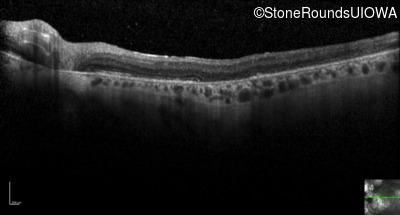

Optical Coherence Tomography - Right - 20/100

Exemplar / OCT Stack